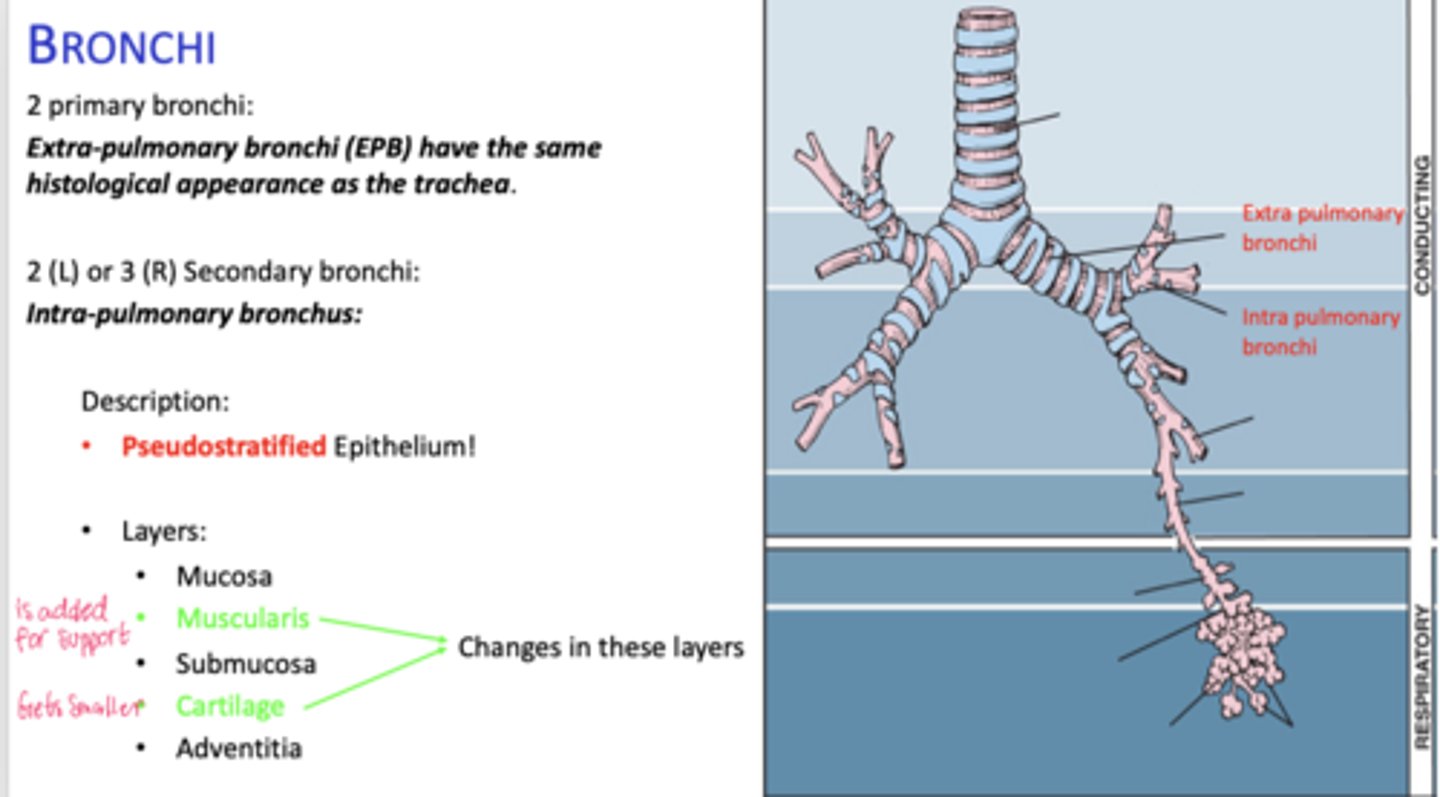

How many primary bronchi are present?

Two

How do extrapulmonary bronchi compare histologically to the trachea?

Same histological appearance.

How many secondary bronchi are in the lungs?

Two on the left, three on the right (intrapolumanry bronchus)

What happens to epithelial height as bronchial diameter decreases?

Cell height decreases.

What happens to cartilage in intrapulmonary bronchi?

Becomes discontinuous plates.

What muscle layer is present in intrapulmonary bronchi?

Spirally oriented smooth muscle.